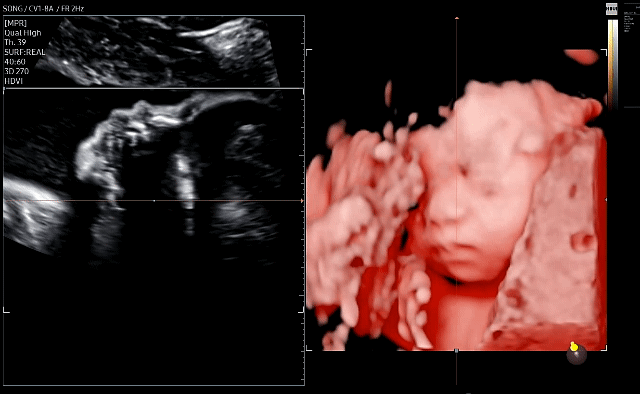

그 다음주에 바로 입체 초음파 2차 시도!

(입체 초음파도 잘 볼 수 있는 시기가 딱 요맘때라더라. 더 크면 보기 힘들다고..)

초음파 선생님은 더 잘 찍어주려고 계속 노력하시는데 (그래서 40분 동안 봤음..!)

사실 난 이정도면 성공했다고 생각해서

중간에는 더 안 보셔도 될 것 같은데..라는 생각이 들긴 했다 ㅋㅋㅋ

그래도 열정적으로 봐주시니까 좋았다 ㅎㅎ

이 날은 다행히 앞쪽을 보고 있긴 했는데

여전히 계속 얼굴 쪽으로 손을 올려서

손을 내리는 타이밍을 잡는 게 쉽지 않았다.

그래도 아무튼 성공!!

우리 딸 이렇게 생겼구나...! 누굴 닮은 건지 전혀 모르겠다.

정면에서 보면 코가 넙적해서 어라? 했는데

초음파 특성상 원래 좀 퍼져보이는 게 있어서 옆으로 돌려보면 안 그렇다며

초음파실 선생님이 열심히 옆으로도 돌려서 예쁜 사진 나오게 해주셨다 ㅋㅋㅋ